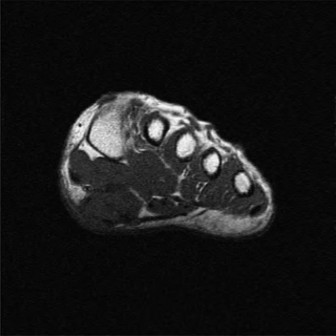

• Magnetic Resonance Imaging (MRI): The gold standard for soft tissue evaluation.

• Precisely characterizes masses (cystic vs. solid, vascularity).

• Assesses PTT integrity (tendinosis, partial tears, full ruptures).

• Evaluates inflammatory changes (bone marrow edema, tenosynovitis).

• Defines relationship of mass to neurovascular structures.

• Image (This image, potentially an MRI, could illustrate PTT pathology or an accessory navicular.)